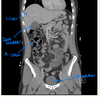

label this CT

Label the: * liver * gall bladder * ascending colon * bladder

label the: * Kidney * Aorta * Stomach * Liver * IVC * Aorta

label the arrows